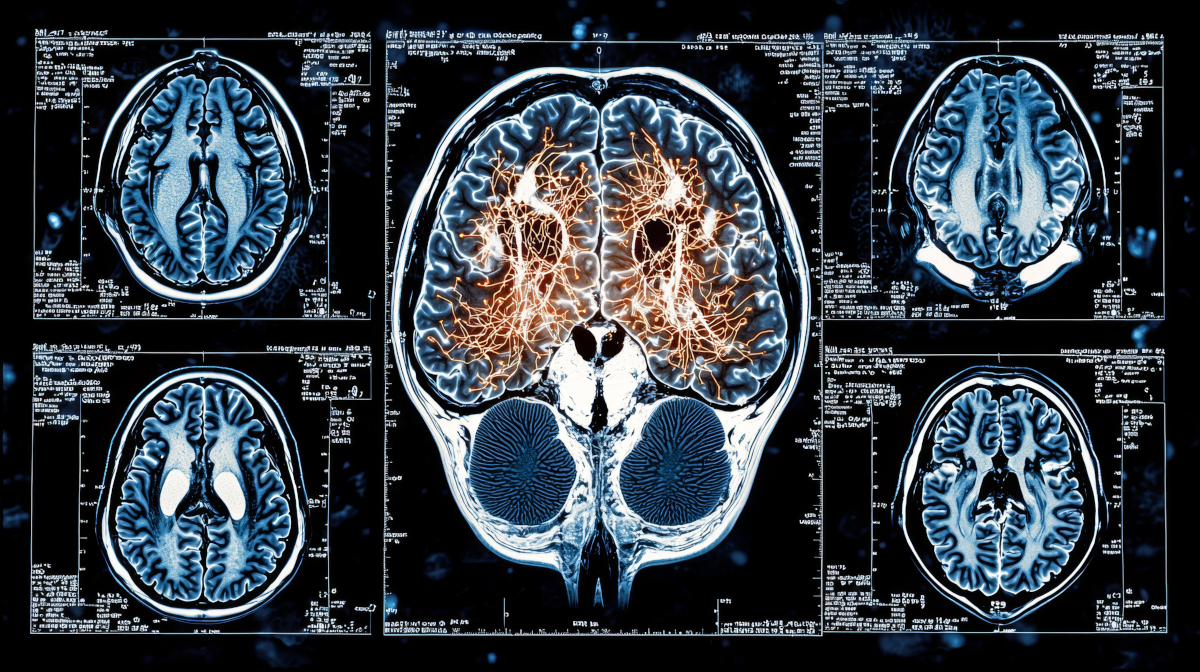

A Journey of Neuroscience in Search of Tomorrow

"A Journey of Neuroscience in Search of Tomorrow"